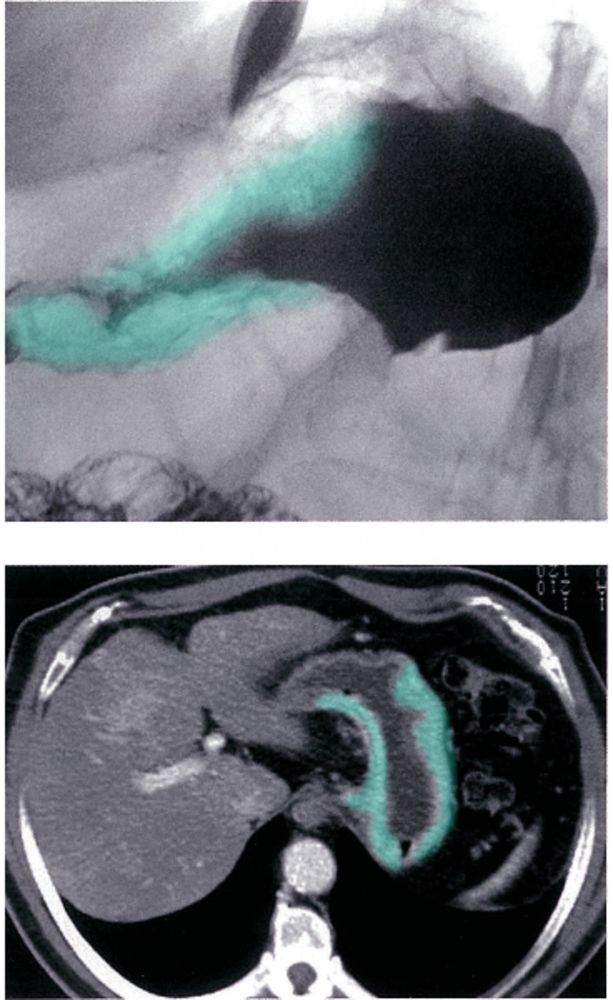

Ménétrier Disease

Hypertophic Gastropathy

(Menetrier Disease)

Foveolar Hyperplasia

Green overlay → foveolar hyperplasia, i.e. hyperplastic antral glands

Green arrows → hyperemia in the lamina propria